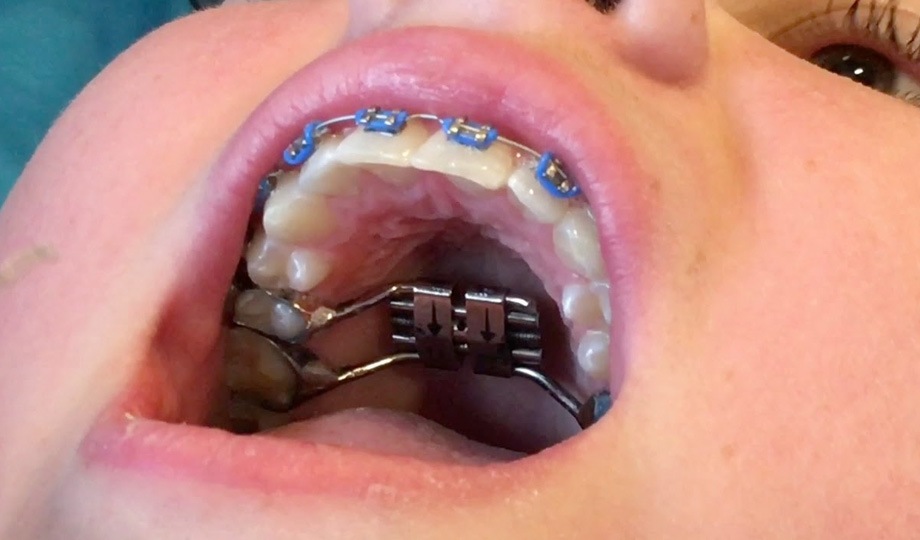

A Expansão Rápida da Maxila (ERM) é um dos procedimentos mais estudados e, ao mesmo tempo, mais discutidos da ortodontia moderna. Embora faça parte da rotina